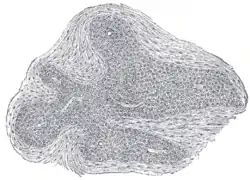

![]() Section of an irregular nodule of the glomus coccygeum. X 85. The section shows the fibrous covering of the nodule, the bloodvessels within it, and the epithelial cells of which it is constituted. | |

It is about 2.5 mm. in diameter and is irregularly oval in shape; several smaller nodules are found around or near the main mass.

It consists of irregular masses of round or polyhedral cells epitheloid cells, which are grouped around a dilated sinusoidal capillary vessel.

Each cell contains a large round or oval nucleus, the protoplasm surrounding which is clear, and is not stained by chromic salts. Since it is not stained by chromic salts, it is not truly a part of Chromafin system; viz. the system which includes cells stained by chromic salts, consisting of renal medulla, para ganglia, and para aortic bodies.